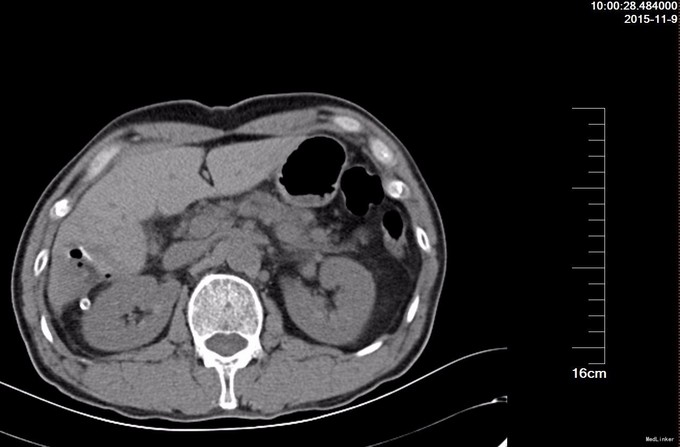

查体: 腹部平坦,未见胃肠型及蠕动波,未见腹壁静脉曲张,全腹软,无压痛,无反跳痛或腹肌紧张,未及腹部肿物,Murphy征阴性。肝脾肾区无叩击痛。移动性浊音阴性。肠鸣音4次/分。 辅查: BUS 提示肝脏大小属正常范围,肝内见多个高回声团,较大者位于右叶,大小约5.6x4.2cm,边界清。 门静脉主干直径约1.0cm。 肝内外胆管未见扩张。 胆囊大小约5.3x1.8cm,壁厚约0.2cm。 脾肋间厚约3.0cm。 胰腺大小、形态正常,主胰管未见扩张,胰腺未见明显占位性病变。

诊断: 肝血管瘤 治疗:全麻下腹腔镜探查,见胆囊无异常,右叶后下段2枚血管瘤,大者直径5.4厘米,外生性,小的直径3厘米,扁平状,左叶脏面可见2厘米扁平血管瘤,术中诊断肝多发血管瘤,2枚较小血管瘤直接腔镜下电烧消除,较大的肝血管瘤继续腔镜下包膜外剥脱。手术时间130分钟,术中失血500毫升。 术后病理,镜下见大小不等,形状不规则的血管,病理诊断:(肝右叶)海绵状血管瘤。

术后复查CT, 肝脏S4段及S6段可见两个低密度占位,与周围肝实质界限欠清,大小分别约25×16mm、51×48mm,前者边缘少量气泡;后者内可见气泡和少量稍高密度影,邻近导管外引流,周围脂肪间隙渗出改变。术后四天腹腔引流20毫升,予以拔除,病人出院。该血管瘤外生性,直径超过5厘米,尽管血管瘤恶变几率很低,但是肝血管瘤确实可以破裂出血,尤其像这样的外生性血管瘤。腔镜下切除肝血管瘤,由于控制出血比较可能,再加上容易破裂,总体上术中出血会比开腹多,手术时间也可能比开腹时间长,但是腹壁无大刀口,术后恢复确实比开腹手术快很多,保守估计,术后至出院时间比开腹手术的缩短1倍,患者受益,值得开展。